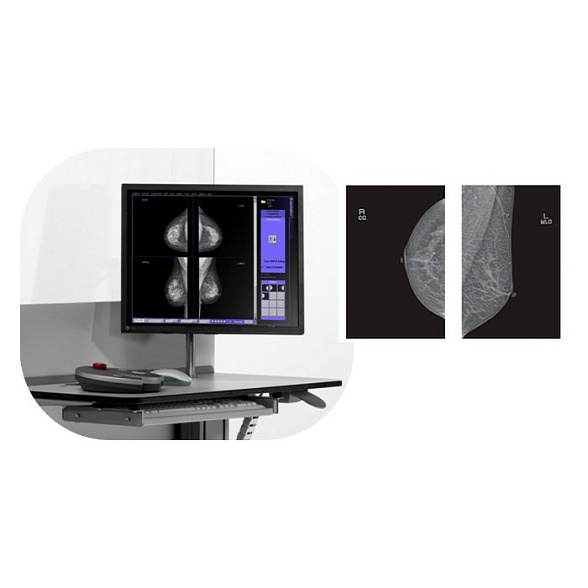

Bemems Pinkview АT Маммограф с комплексом компьютерной радиографии

Bemems Pinkview AT: Цифровой маммограф с комплексом компьютерной радиографии

Маммограф Bemems Pinkview AT представляет собой современную цифровую систему для ранней диагностики заболеваний молочной железы. Это комплексное решение, объединяющее в себе высокотехнологичный маммографический аппарат и рабочую станцию компьютерной радиографии (КР), что обеспечивает полный цикл получения и обработки диагностических изображений.

- Повышение производительности: Мгновенное получение изображения на монитор врача исключает время на проявку пленки, ускоряя процесс обследования и снижая вероятность технического брака.

Встроенная система компьютерной радиографии — это не просто сканер, а интеллектуальное звено, преобразующее информацию с imaging plate (CR-кассеты) в цифровой DICOM-файл. Комплекс включает в себя считывающее устройство, рабочую станцию со специализированным программным обеспечением для обработки и просмотра изображений, а также набор многоразовых CR-кассет. Это решение идеально подходит для модернизации существующих пленочных маммографов до цифрового уровня или для создания гибкой диагностической сети.

| Режимы съемки | Стандартные проекции: краниокаудальная (CC) и медиолатеральная косая (MLO). Возможность прицельной и увеличенной маммографии. |

| Программное обеспечение | Включает ПО для управления аппаратом, считывания CR-кассет, обработки, просмотра, архивации и передачи DICOM-изображений. |

Входит ли в комплект рабочая станция врача?

Да, комплекс компьютерной радиографии включает в себя рабочую станцию (компьютер, монитор медицинского класса, считывающее устройство и ПО), необходимую для обработки и анализа полученных изображений.